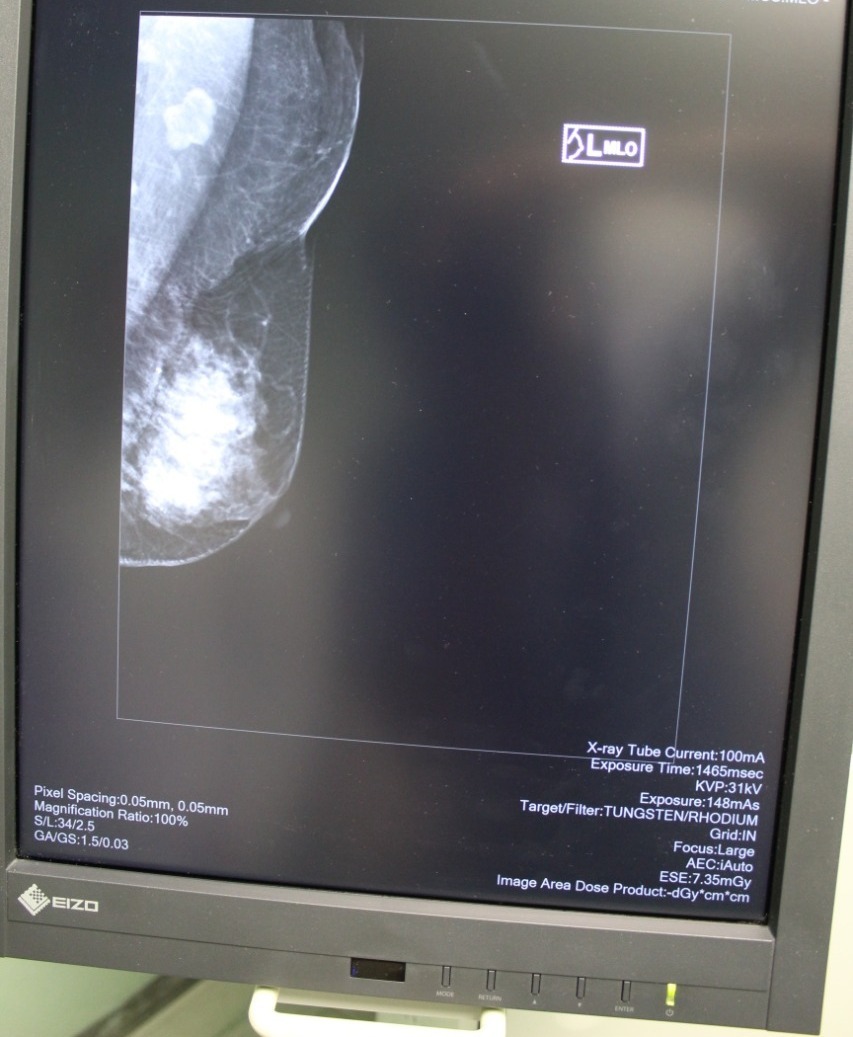

Las guías a nivel internacional – añadió -, nos dicen que una mujer debe empezar a explorarse incluso desde los 18 años; a partir de los 25 ya se recomiendan estudios de imagen y a partir de los 40 años es muy importante que todas las mujeres se realicen una mastografía anualmente.

Destacó que en el Hospital Regional de Alta Especialidad “Ciudad Salud” se ofrece desde estudios diagnósticos como la mastografía, hasta la toma de biopsia de tumores sospechosos de cáncer; y una vez que se confirma el diagnóstico, se brinda tratamiento médico – quirúrgico y se deriva, si es necesario, a radioterapia.